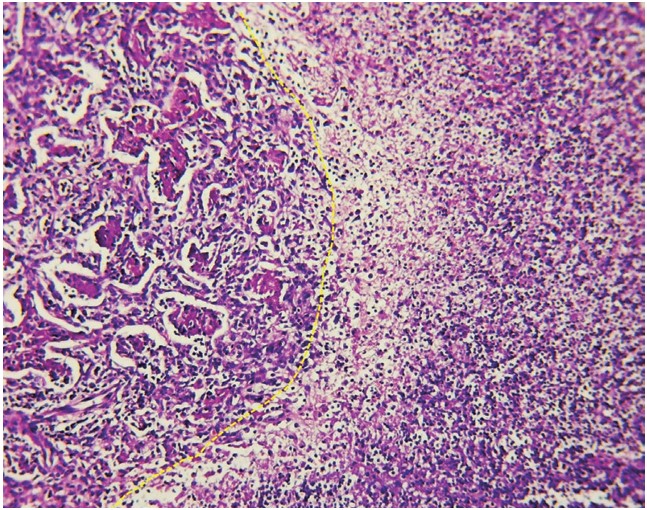

El reporte histopatológico del tejido pulmonar advirtió infiltrados celulares y vasculares, compatibles con un proceso neumónico y necrosis (Figura 1 y 2). El cultivo de la biopsia pulmonar identificó Streptococcus salivarius y Streptococcus viridans. Luego de 18 días de hospitalización egresó por mejoría clínica.

Figura 2 Figura 2. Imagen microscópica con H&E en seco débil (10x) en donde se puede apreciar una zona de transición del proceso neumónico entre zonas de neumonía en vías de organización (lado izquierdo) y zonas necrotizantes de la misma (lado derecho). Observe la pérdida de arquitectura alveolar en la zona necrótica y los agregados fibrinoides intraalveolares de la zona en organización.